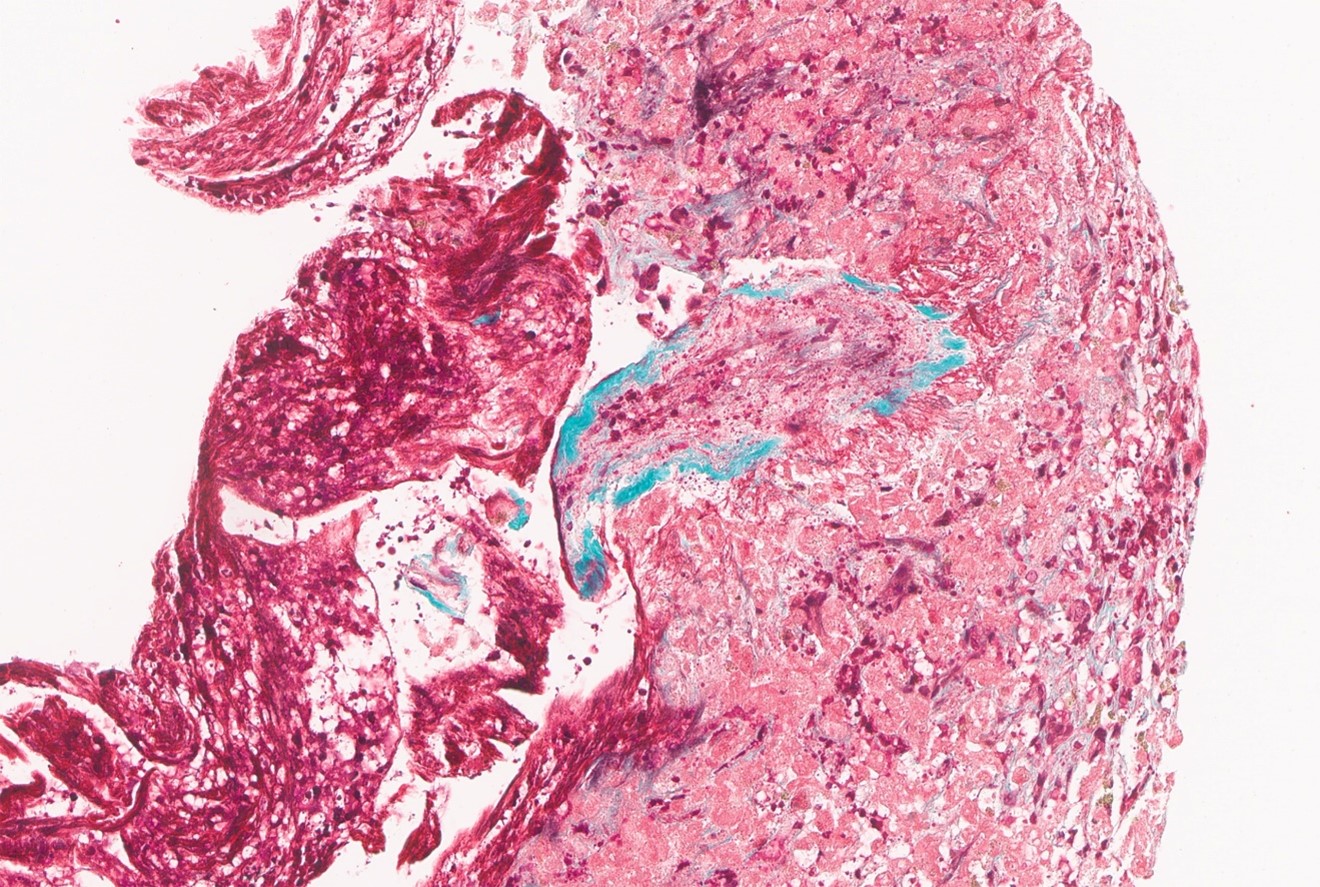

ALF was responsive to ablation of CAR-T cells using cyclophosphamide. She required intubation, vasopressor support, and CRRT. Over 2 weeks, INR declined to <2, allowing decreasing support with blood products. Bone marrow showed B-ALL remission, with presence of some CAR-T cells. She then developed new ascites with PV reversal of flow on US 2 weeks after the onset of ALF. Cholestasis worsened as ascites progressed requiring a peritoneal drain, an overall picture consistent with VOD. Bilirubin peaked at 27.1 almost 2 weeks after ALF declining to 20.9 mg/dL following 10 days of defibrotide. Venogram wedge pressure and endoscopy for variceal bleeding confirmed the presence of portal hypertension. Transjugular liver biopsy demonstrated pericentral necrosis with obstructive changes in hepatic venules but preserved triads, confirming VOD.